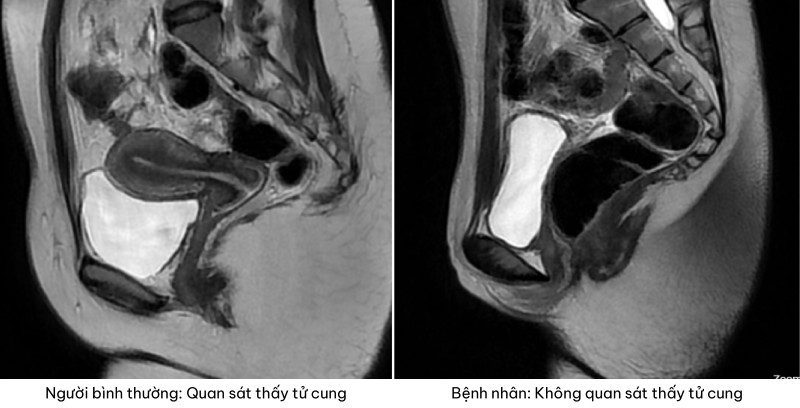

Đáng chú ý, hình ảnh nội soi thực quản phát hiện tổn thương u sùi loét chiếm 3/4 chu vi lòng thực quản kéo dài xuống dưới một đoạn khoảng 7cm gây hẹp lòng thực quản, bề mặt nham nhở mất cấu trúc, chạm vào cứng chắc, dễ chảy máu. Nhận thấy có dấu hiệu ác tính, bác sĩ tiến hành sinh thiết 03 mảnh vùng tổn thương làm mô bệnh học xác định bản chất.

Kết quả nội soi thực quản của bệnh nhân có tổn thương u sùi loét

Kết quả mô bệnh học cho thấy mô u xuất phát từ lớp biểu mô, các tế bào sắp xếp mất cực tính tạo thành đám, mảng. Các tế bào u hình đa diện với nhân lớn, kiềm tính, mảng nhân méo mó, tỷ lệ nhân/ bào tương tăng, một số vùng thấy cầu nối gian bào hoặc hình ảnh cầu sừng. Giải phẫu bệnh kết luận Carcinoma vảy sừng hóa xâm nhập.

Dựa vào các kết quả cận lâm sàng và “tiêu chuẩn vàng” là giải phẫu bệnh, bác sĩ chẩn đoán xác định bệnh nhân mắc Ung thư thực quản nghi ngờ di căn phổi. Bệnh nhân được khuyến nghị làm thêm hóa mô miễn dịch với PD-L1 để phục vụ tiên lượng và điều trị.